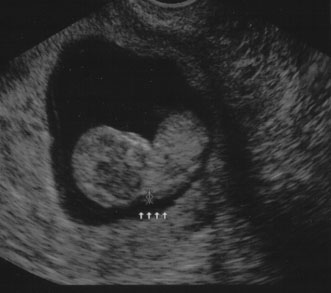

Maternal serum screening can identify pregnant women who are at an increased risk for having a baby with certain birth defects. Patient-specific risks for open spina bifida, Down syndrome and trisomy 18 (Edwards syndrome) (Fig. 1) can be determined by measuring the levels of certain proteins in maternal serum and combining those data with the patient's maternal age and clinical information.10 Women with a positive screen should be offered a definitive diagnostic test.

Fig. 1. Three-dimensional ultrasound showing typical pattern of trisomy 18. A clenched fist with the index finger overlapping the third and fourth fingers is distinctive of this disorder. Image courtesy of GE Medical Systems.